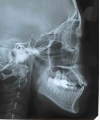

治療前後の比較